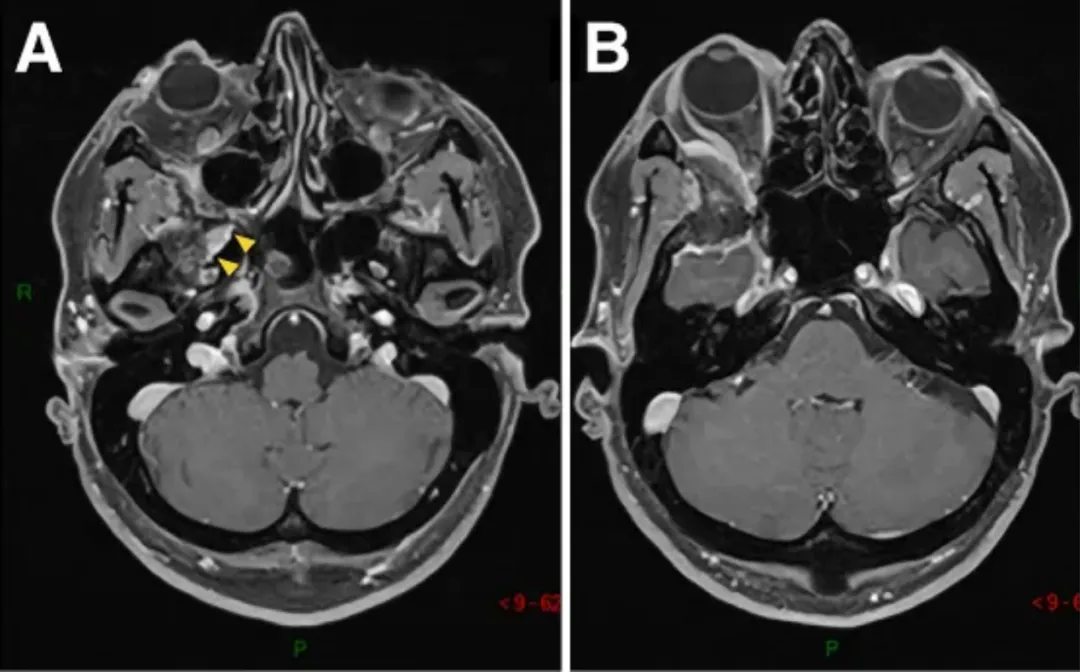

图1A-D:术前MR显示蝶眶区肿瘤占位,增强均匀病灶,浸润延伸至翼腭窝(黄色箭头)。

E-H:术后轴位MR图像显示肿瘤完全切除。